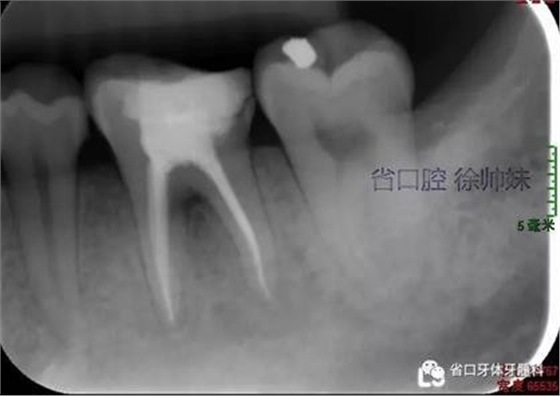

根尖片(圖4)示36根尖周低密度影明顯較前消退,根分叉仍有少許低密度影。

圖4 術后4月